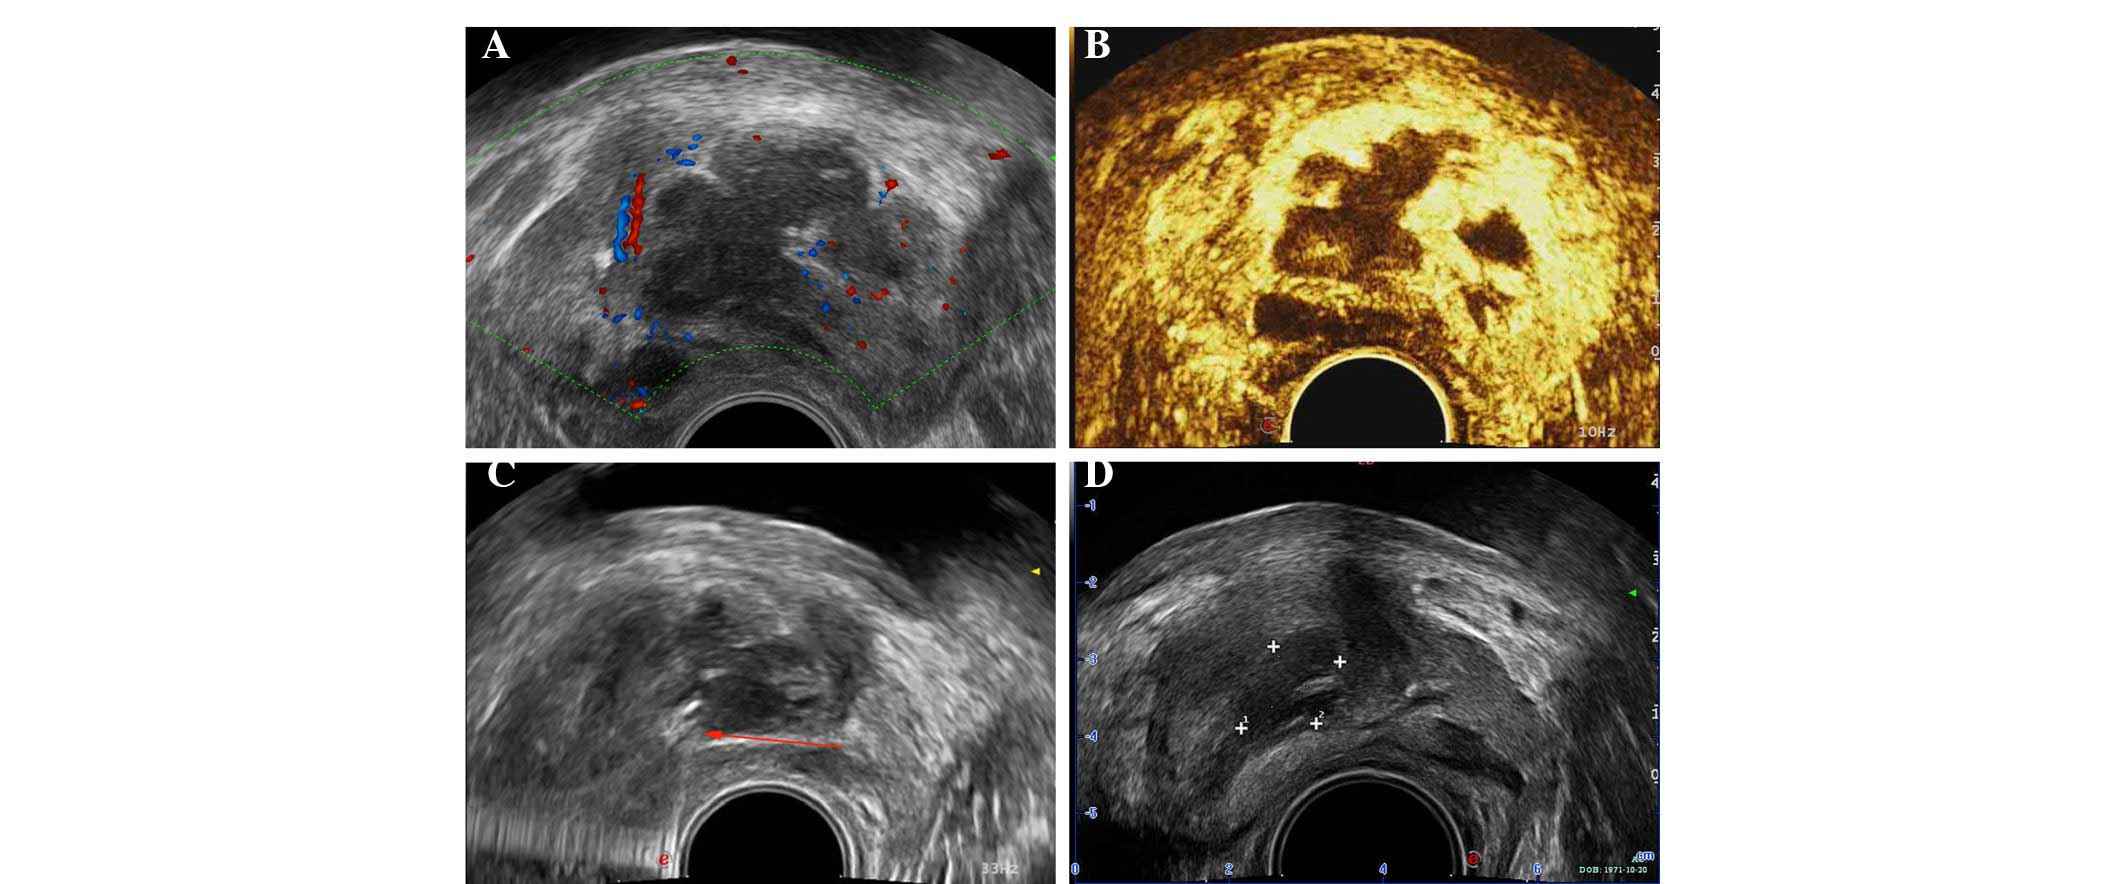

Абсцесс предстательной железы как лечить - фото презентация